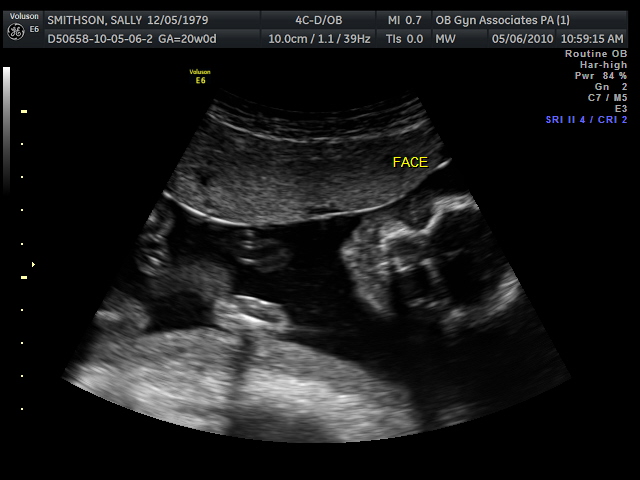

So, with all that being said...guess what? We're expecting! Not only that, but as of last Thursday, we found out that our new little peanut is A GIRL! That's right, Abigail will soon have a little sister to play dress up with. We couldn't be more excited. Coming from a house full of boys, I'm excited for Abigail to be able to have a sister/friend to travel through life's ups and downs with. While Josh is now busy wondering how on earth we will ever be able to pay for 2 weddings someday, I am busy fretting over what our life is going to look like 16 years from now when these two little angels become teenagers in high school. And I only thought my life was full of drama now...

We received a good report from the last sonogram. Not only am I continuing to gain weight (which pleases the doctor), baby girl is healthy and measuring right on track. I am currently 20 1/2 weeks along and my due date is set for September 23rd.